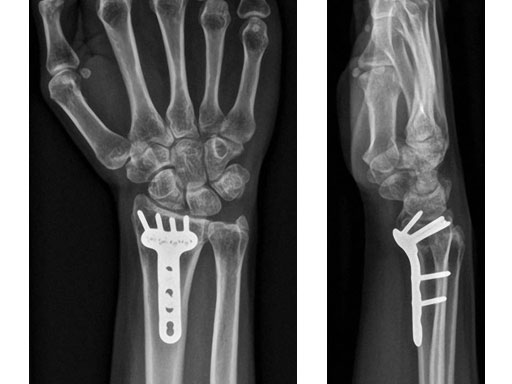

Fig 2ab X-rays postoperatively.